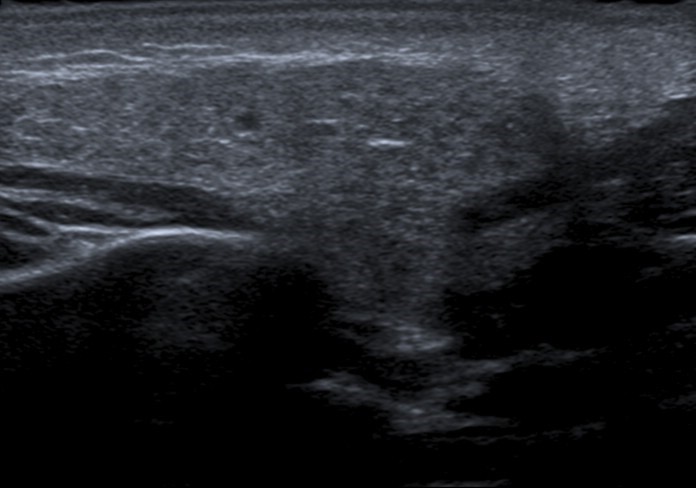

Entre las pruebas complementarias solicitadas para estudio de parotiditis recurrente, se realizó una ecografía cervical que mostraba una glándula discretamente aumentada de tamaño, de ecoestructura heterogénea e hipoecogénica que presentaba pequeñas áreas hipoecoicas en su interior que correspondían a sialectasias o infiltración linfocitaria (Fig. 1).

| Figura 1. Ecografía cervical. Glándula discretamente aumentada de tamaño, de ecoestructura heterogénea e hipoecogénica que presenta pequeñas áreas hipoecoicas en su interior, correspondientes a sialectasias o infiltración linfocitaria |